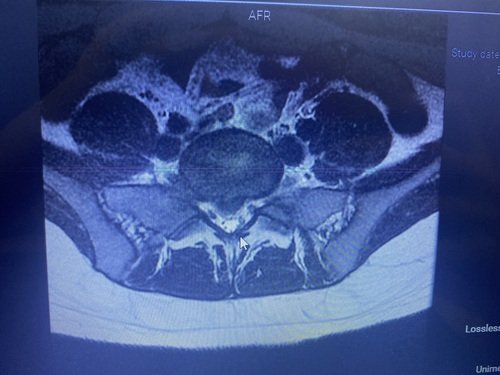

Olá, sou a Thainar, tenho 24 anos. Estou desde o dia 04/10/2023 em casa por complicações na minha coluna. Uma hérnia de disco aumentou bastante na minha coluna, gerando uma extrusão onde aperta o meu nervo ciático e acabou inflamando o nervo.

Desde quarta os remédios (que não são poucos que estou tomando e nem baratos) não estão mais ajudando e estou de cama. Pois a dor é terrível (começa a dor na lombar, queima e da pontada até a ponta do pé). E não tenho outra forma de resolver a não ser passando pela cirurgia.